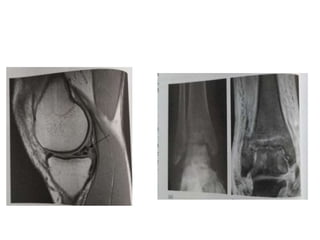

MAGNETIC RESONANCE IMAGING (

• Provides superb soft tissue contrast , distinguishing

different soft tissues eg. Ligaments , tendons ,

muscle & hyaline cartilage

CLINICAL APPILICATIONS OF MRI

• Ideal for non – invasive imaging of the musculoskeletal system - excellent

anatomical detail , soft tissue contrast & multiplanar capability

• MRI of hip , knee , ankle , shoulder & wrist is common - can detect early

changes of bone marrow oedema & osteonecrosis

• MRI Knee - for meniscal tears & cruciate ligament injuries

• Fat suppresion sequences – extent of perilesional oedema & IV contrast –

active part of the tumour ( it distinguish vascular from avascular tissues

• Direct MRI arthrography - distent joint capsule

diagnose labral tears in shoulder & hip

ankle – assess integrity of the capsular ligaments

MAGNETIC RESONANCE IMAGING( MRI ) • Provides superb soft tissue contrast , distinguishing different soft tissues eg. Ligaments , tendons , muscle & hyaline cartilage • Utilizes Non – Ionizing radiation • Contraindicated in patients with pacemakers & possible metallic foreign body

CLINICAL APPILICATIONS OFMRI • Ideal for non – invasive imaging of the musculoskeletal system - excellent anatomical detail , soft tissue contrast & multiplanar capability • MRI of hip , knee , ankle , shoulder & wrist is common - can detect early changes of bone marrow oedema & osteonecrosis • MRI Knee - for meniscal tears & cruciate ligament injuries • Fat suppresion sequences – extent of perilesional oedema & IV contrast – active part of the tumour ( it distinguish vascular from avascular tissues • Direct MRI arthrography - distent joint capsule diagnose labral tears in shoulder & hip ankle – assess integrity of the capsular ligaments